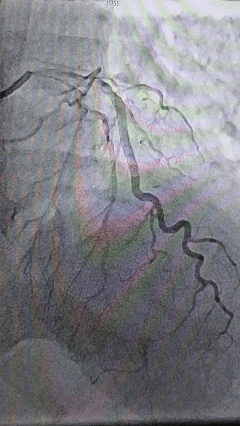

进入介入科后,冠脉造影结果显示,患者的前降支已从近段完全堵死,情况十分紧急。心内科团队迅速展开手术,穿刺、造影、球囊扩张、支架植入……每一个步骤都精准而迅速。对于心率过慢、血压过低的患者,手术风险极高,操作需如履薄冰。团队不仅要争分夺秒地开通被血栓堵塞的冠状动脉,恢复心肌供血,还要时刻维持患者生命体征的稳定,应对术中可能出现的任何突发状况。随着血流恢复,患者的心率、血压逐步回升,成功为患者开通了闭塞的“生命线”。

IMG_258 术后